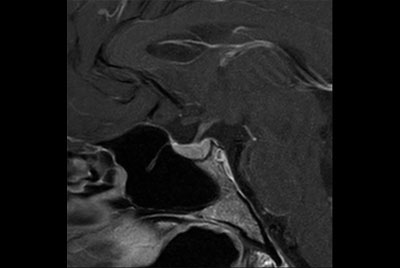

Neck stenosis